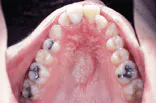

The problem: Intraoral examination revealed a large, diffuse lesion. The lesion appeared to be erosive and ulcerated.

The problem: Examination of the occlusal radiograph revealed a large well-defined radiolucency.

The problem: Oral examination revealed shiny gingiva with a lack of stippling in the area of involvement.

The problem: Radiographic examination revealed mixed lucent-opaque lesions around the apices of teeth #24 and #25.